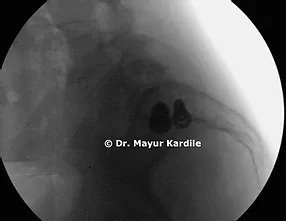

The patient had good pain relief after the surgery and got back to her normal life within a few weeks.

MIS SI joint fusion is done through a 3 cm incision in the buttock area. In carefully selected patients, this procedure can give gratifying results.